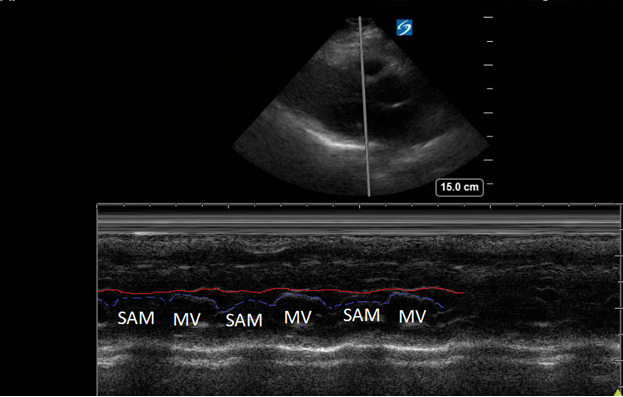

A point-of-care ultrasound was performed to evaluate for potential etiologies of syncope. The ultrasound displayed biventricular and interventricular septal hypertrophy (Figure 2), systolic anterior motion of the mitral valve (SAM, Figure 3), and a “dagger-like” continuous wave Doppler waveform emerging from the left ventricular outflow tract. (LVOT, Figure 4)

Figure 3. Parasternal long-axis view using M-Mode displaying SAM of the mitral valve against the interventricular septum (red line). Note how the mitral valve shifts anteriorly during the same period that the septum contracts posteriorly.

Hypertrophic obstructive cardiomyopathy (HOCM) refers to the common obstructive subset that affects 70% of patients with HCM.6 Left ventricular outflow tract obstruction (LVOTO) has been shown to be an independent predictor for adverse outcomes by multiple studies.7 Traditionally, systolic anterior motion (SAM) of the mitral valve was thought to be pathognomonic for HCM. Recent studies have shown that of the HCM patients with SAM, 25-50% will have LVOTO.8 Using ultrasound, SAM is observed in the parasternal long-axis using M-mode over the anterior leaflet of the mitral valve. The time the valve is contact with the septum quantifies disease severity.

1) Mild: brief SAM without septal contact

2) Moderate: septal contact < 1/3 of systolic period

3) Severe: septal contact > 1/3 of systolic period9